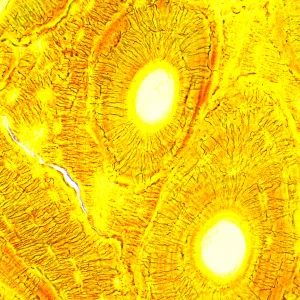

Биологический микроскоп MAGUS Bio 250B – оптический инструмент для изучения тонких прозрачных и полупрозрачных объектов. Основной метод исследований – светлое поле в проходящем свете. Микроскоп можно оснастить дополнительными аксессуарами для использования методов темного поля, фазового контраста и поляризованного света. Высококачественная оптика с дополнительными опциями, расширяющими ее возможности, удобная механика и продуманная конструкция делают этот микроскоп отличным выбором для лабораторной работы, научных исследований и обучения студентов.

Большой выбор аксессуаров позволяет настроить возможности MAGUS Bio 250B наиболее удобным для пользователя образом. Доступны окуляры, объективы, устройства для работы по методам темного поля, фазового контраста и поляризованного света, калибровочные слайды, цифровые камеры.